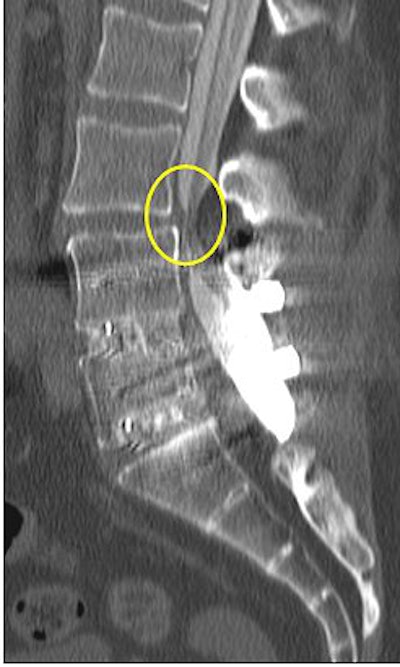

| Above, nonaxial loaded CT scan of postsurgical lumbar fusion patient showing increased stenosis of the thecal sac at the L3-L4 level with axial loading (below). |

A survey of patients from a private practice setting who underwent axial-loaded imaging demonstrated an increase in the conspicuity of focal disk bulging and herniation, as well as an increase an anterolisthesis or retrolisthesis ("Axial loaded magnetic resonance imaging of the lumbar spine in a chiropractic patient population," Proceedings of the 2006 Conference on Chiropractic Research, Chicago).

Dr. Akio Hiwatashi's group found that axial loading during MR imaging of the lumbar spine can influence treatment decisions for symptomatic spinal stenosis from conservative management to decompressive surgery based on the findings obtained from axial-loaded MR images (American Journal of Neuroradiology, February 2004, Vol. 25:2, pp. 170-174).